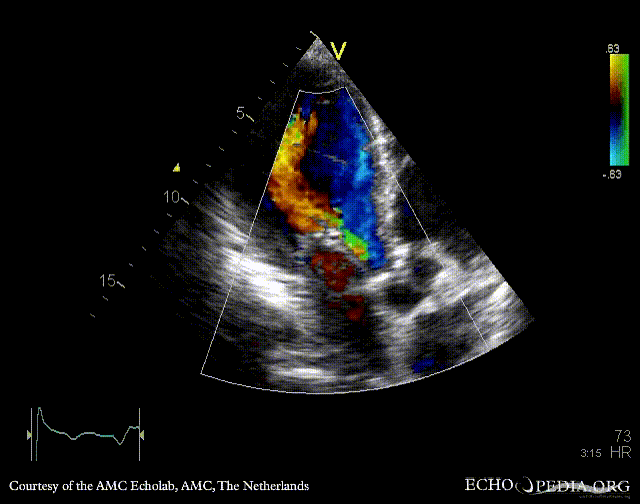

E00437.gif E00438.gif

A4CH: enlarged atria and ventricles A3CH: severe aortic and mitral regurgitation